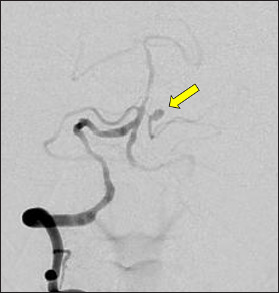

Case description: A 77-year-old woman presented with a sudden headache and computed tomography showed a subarachnoid hemorrhage predominant in the left cerebellopontine angle. Cerebral angiography revealed a saccular aneurysm in the anterior pontine segment of the left AICA. Coil embolization underwent preserving the parent artery. There is no recanalization of the aneurysm at 26 months postoperatively. In this case, hemodynamic stress was suggested to be involved in the development of the aneurysm.